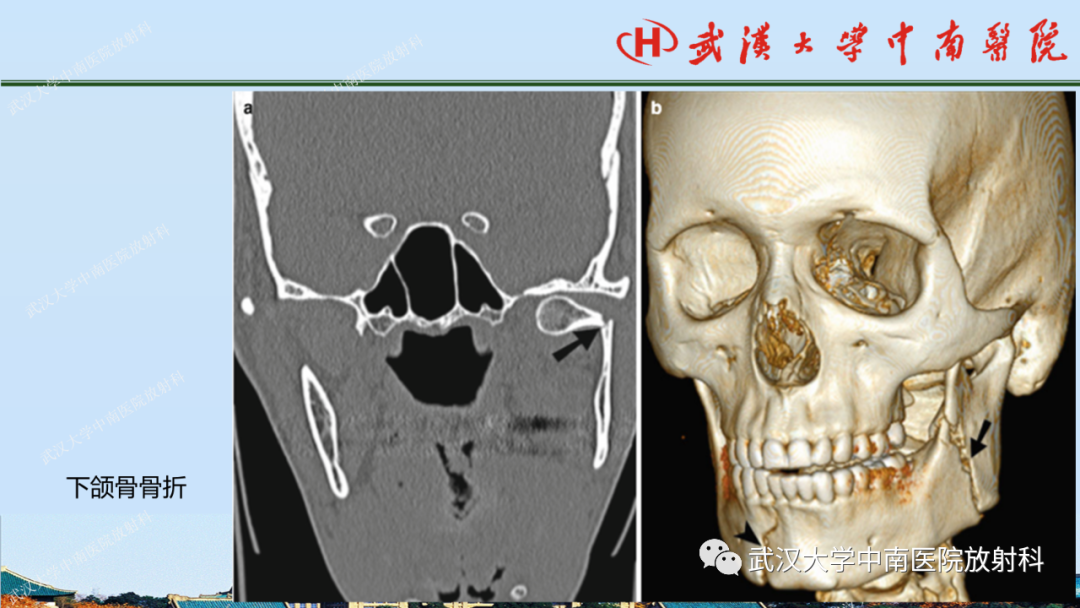

【PPT】脑外伤影像学诊断